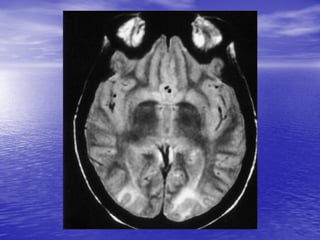

This document discusses the management of intracranial pressure and cerebral edema in neurocritical care patients. It covers topics such as how patients typically present with brain injuries, important caveats in neurological examinations, principles of cerebral resuscitation, mechanisms of primary and secondary brain injury, the pathophysiology over time, imaging techniques including CT scans and MRI, monitoring techniques like intracranial pressure monitoring, and treatment approaches like the use of hyperosmolar therapy with mannitol or hypertonic saline. The goal is to prevent secondary brain injury after the initial primary injury occurs.